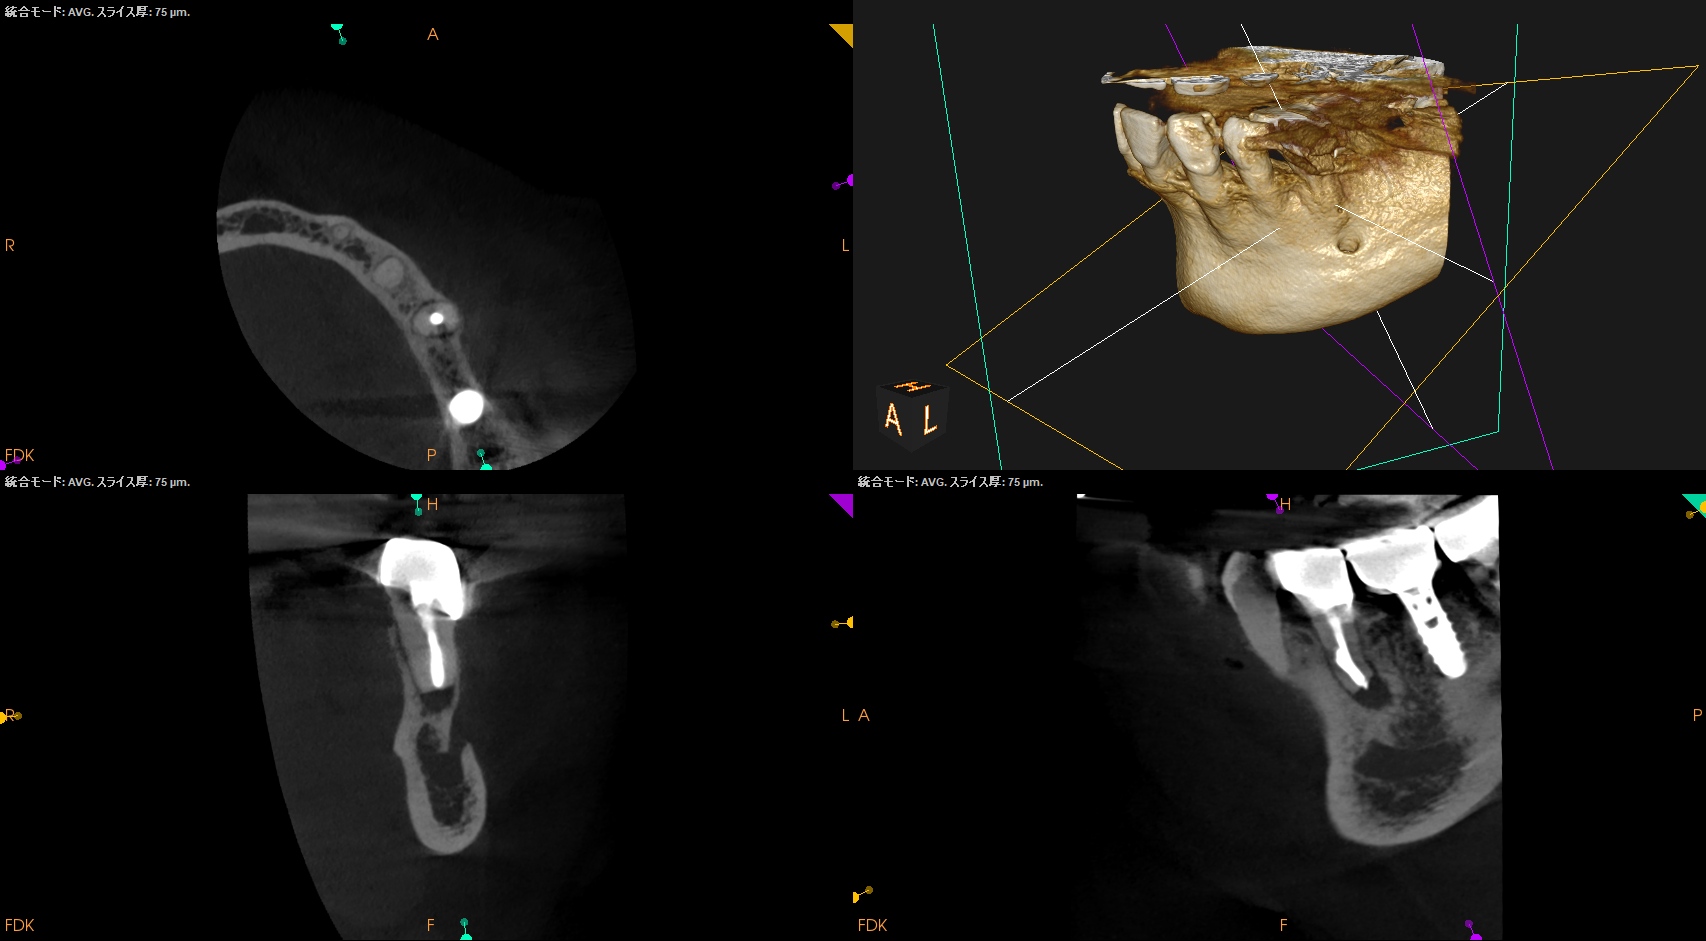

では、CBCTではどうだろうか?

Apicoectomyは不可能だ。

オトガイ孔を傷つけるリスクがあるからだ。

術後のPA, CBCTは以下である。

問題はないだろう。